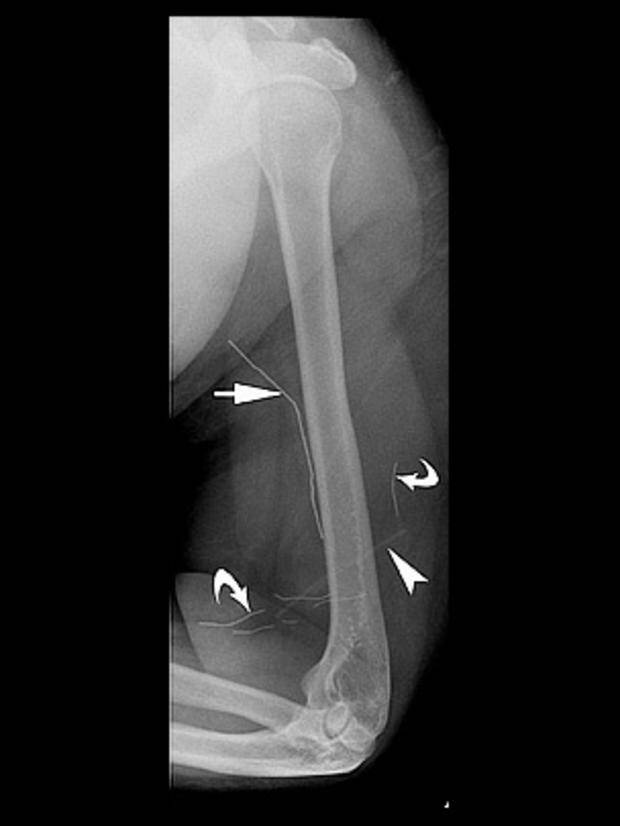

– Okres dojrzewania może być niezwykle stresujący – powiedział dla CBS News dr William E. Shiels, szef radiologii w Nationwide Children’s Hospital w Colombus (Ohio). Jest on autorem nowego badania na temat zachowań zagnieżdżania w sobie przedmiotów, które zostało opublikowane w czasopiśmie Pediatrics. – Dzieci mówią nam, że ból fizyczny jest łatwiejszy do zniesienia niż ból emocjonalny. Umieszczenie w sobie jakiś obiektów odwraca ich uwagę od bólu psychicznego.

Shiels jest pionierem w stosowaniu technik chirurgicznych do usuwania osadzonych w ciele przedmiotów. We wspomnianym wywiadzie przyznał, że jest zdumiony, że aż co czwarty nastolatek w Stanach Zjednoczonych popełnia jakąś formę samookaleczenia. Nie chodzi tu tylko o umieszczenie czegoś pod skórą, ale również o skaleczenia, poparzenia czy inne formy samoranienia. Ta jedna-czwarta nastolatków odnosi się do całej populacji młodzieży w USA – a nie tylko do tych, który byli fizyczne czy psychicznie katowani, wykorzystywani seksualnie czy u których zdiagnozowano afektywną chorobę dwubiegunową, zaburzenia lękowe, zaburzenia osobowości czy inne trudności na bazie psychiki.

Samookaleczenia są niebezpieczne – oprócz ryzyka wywołania infekcji, umieszczanie w ciele przedmiotów może uszkodzić nerwy lub naczynia krwionośne. – W skrajnych przypadkach oprócz krwawienia (w tym wewnętrznego) może wystąpić nawet udar – powiedział Shiels.